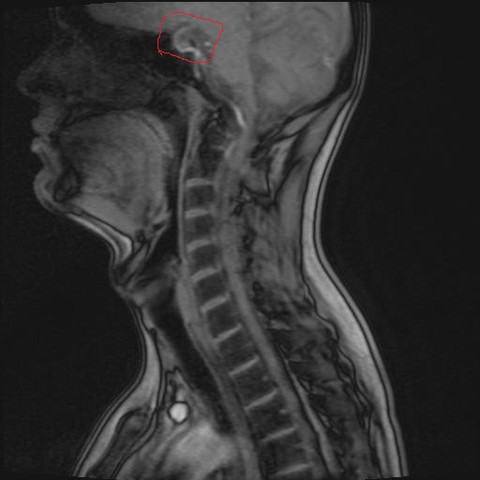

Hallo Vor Kurzem Wurde Ein Mrt Von Meiner Wirbelsaule Angefertigt Dann Habe Ich So Etwas Komisches Gefunden Ist Das Ein Hirntumor Oder Gehort Das Zum Gehirn Hws Ct Halswirbelsaule

Hirntumor Mrt T1 Gewichtet Mit Kontrastmittel Sagital Kampf Dem Glioblastom